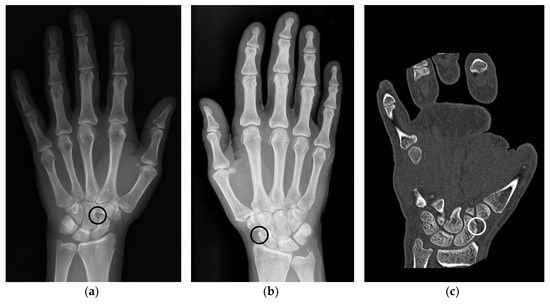

Figure 2. Examples of anatomical pseudoerosions. (a) Example of a sulcus like pseudoerosion of the capitate bone (black circle) in a left hand of a 52 years old female patient. Referred for suspected scaphoid fracture, which was not verified. (b) Example of a pseudoerosion at the level of the scaphoid waist (black circle) in a right hand of a 66 years old female patient. Referred because of unspecific wrist pain, which afterwards subsided without treatment after one week. (c) Scaphoid rim simulating an erosion in a left hand of a 38 years old male patient (white circle). Referred because of presurgical planning after fracture of the fifth metacarpal and luxation of the fourth and third metacarpal.

3.1. Anatomic Pseudoerosions

Anatomic pseudoerosions, i.e., normal concavities of a bone with a potential for misinterpreting them as arthritis-related erosions, were described in twelve original papers and reviews and may be classified into four types according to their anatomic form and configuration (Table 1): (1) a groove or notch or its incomplete form, i.e., a jutty, (2) a sulcus as part of an osteofibrous channel, (3) a subcapital neck on long bones, or (4) a nutritional channel or a zonal roughness [3,11,41,51,52,53,54,55,56,57]. According to their shape, they may be grouped into (1) shallow or broad concavities and (2) subchondral cysts, if en-face displayed on an image and occasionally with a small opening to the joint space, or (3) channel-like structures (Figure 2a,c) [3,54,55]. The anatomic location of pseudoerosions is predominantly at the carpal bones, the MCP- and the MTP-joints. Almost always they are linked to a ligament insertion (Figure 2b), a mucosal fold fixation or the hood of a tendon sheath, and occur at the noncortical bone, also known calcified zones (i.e., borders of the subchondral and enthesial calcified bone with the adjacent underlying trabecular structures). The content of pseudoerosions is visible with US and MRI and may be normal or degenerated ligament tissue, or blood vessels [44,56] and the development of edematous changes [58]. With contrast media, a slight enhancement can be observed, however, in one publication rare cases of strong enhancement was documented [56].